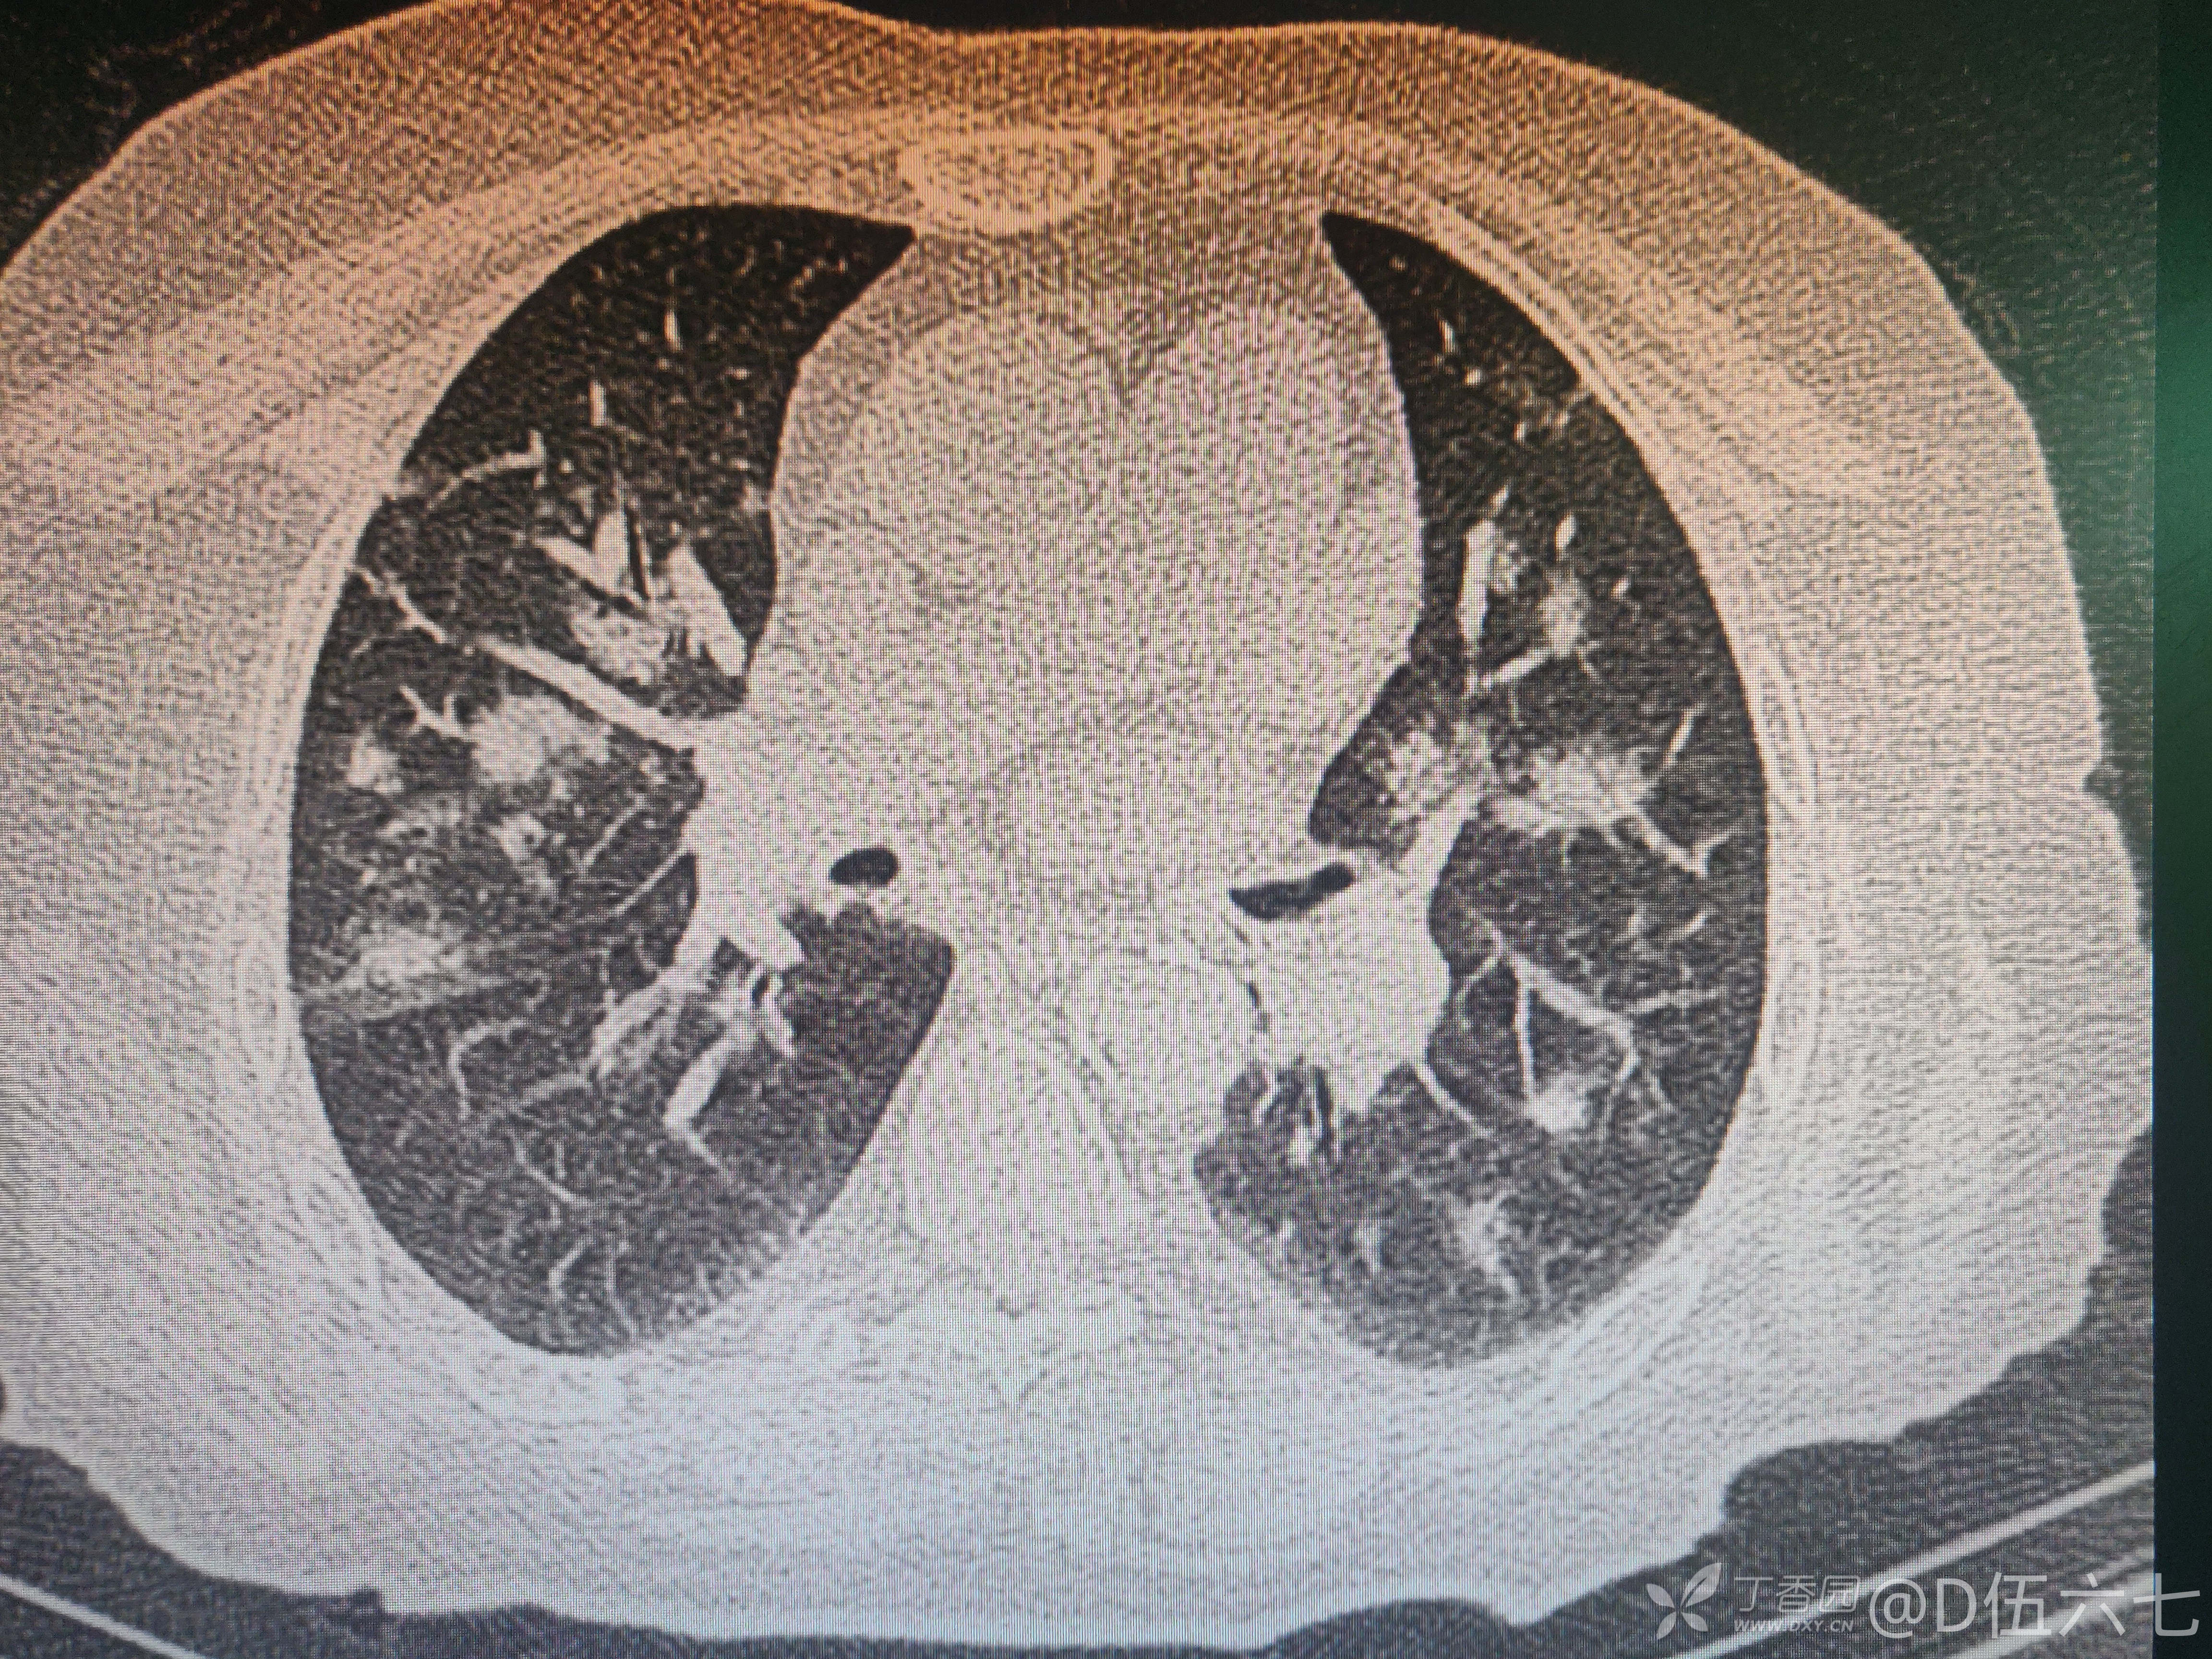

老年女性,多发肺部阴影

李梦杰huxi 达人已点赞68岁女性,有糖尿病、脑梗塞史,平素胰岛素控制血糖,血糖控制不稳定。三天前无明显诱因低热一次,后未再出现发热,近两日来失声、呼吸急促来诊,急诊测SpO2 92%,右肺痰鸣音。

请各位大佬分析影像特点

金葡?结核?真菌?其他?